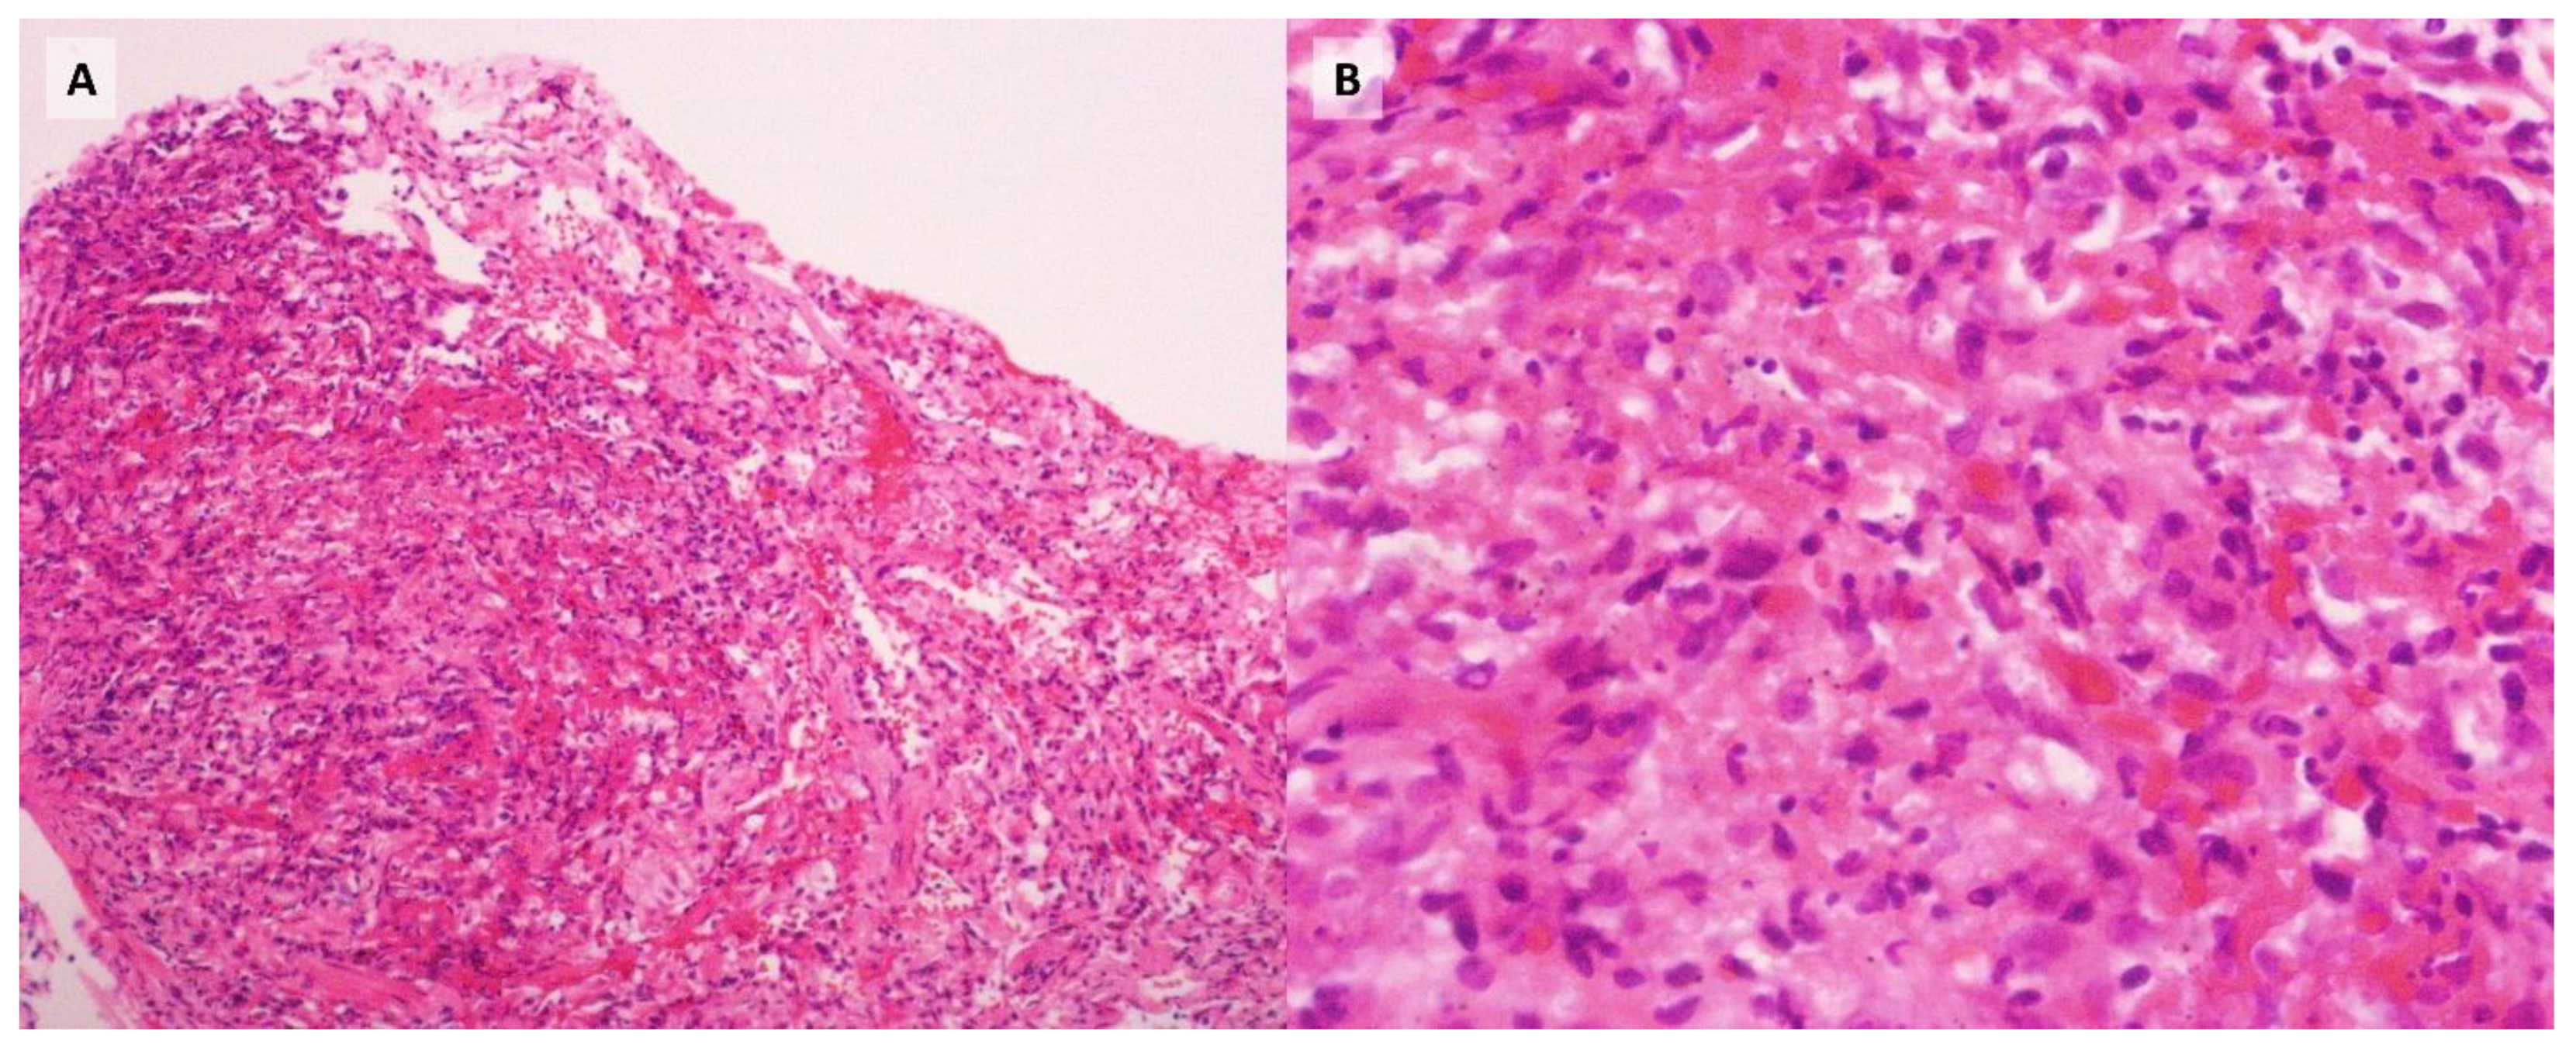

Despite targeted therapy, the patient experienced progressive clinical deterioration, ultimately developing respiratory failure that required orotracheal intubation and admission to the intensive care unit (ICU) on day 10 of hospitalization. By day 12, the report was received. Subsequent transbronchial biopsies were positive for Pneumocystis jirovecii and fungi morphologically consistent with Histoplasma (Figure 2, Figure 3), with no other infectious agents detected in the BAL samples or the blood and bone marrow cultures. Consequently, antifungal therapy was adjusted to include liposomal amphotericin B (5 mg/kg/day) and itraconazole (200 mg tid). However, despite intensive therapeutic interventions, the patient's condition continued to worsen, culminating in a fatal outcome on day 31 of her hospitalization.

Figure 2. Histopathological findings of lung tissue. (A) Hematoxylin and eosin stain, 10X magnification: pulmonary parenchyma with granulomas. (B) Hematoxylin and eosin stain, 40X magnification: higher magnification showing granulomas within the pulmonary parenchyma.